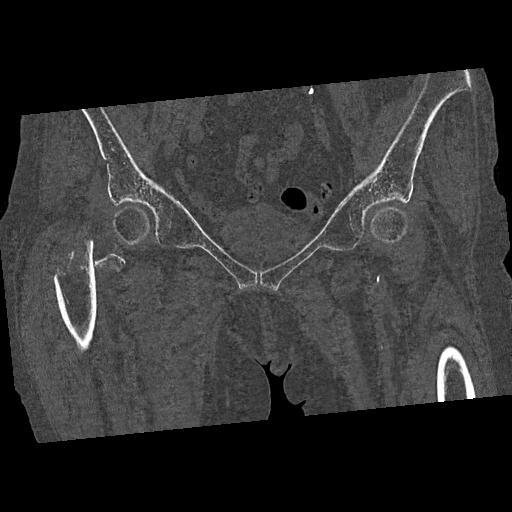

100703 1/27 両股正面+軸 1/29 両股正面+軸 94歳女性 パンソンロン